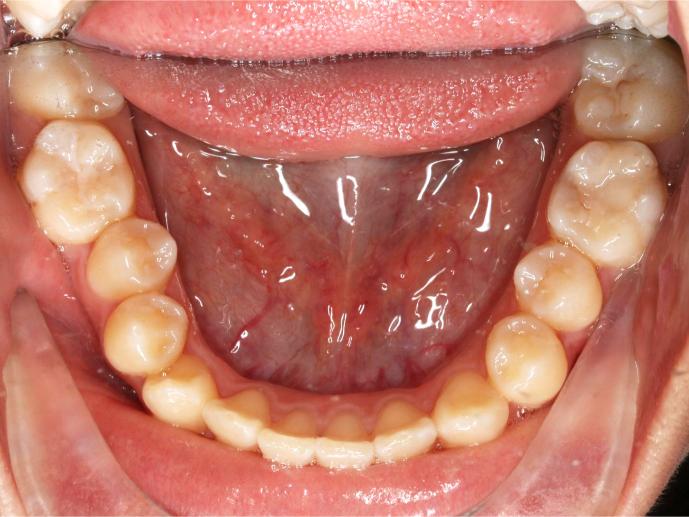

Before and After Images